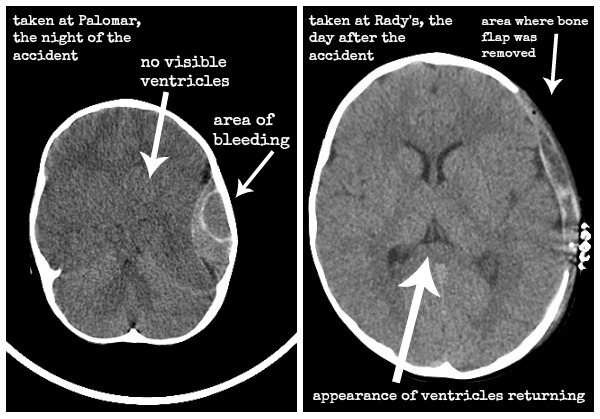

Simon’s before and after CT scans

Simon’s Story: Part Six